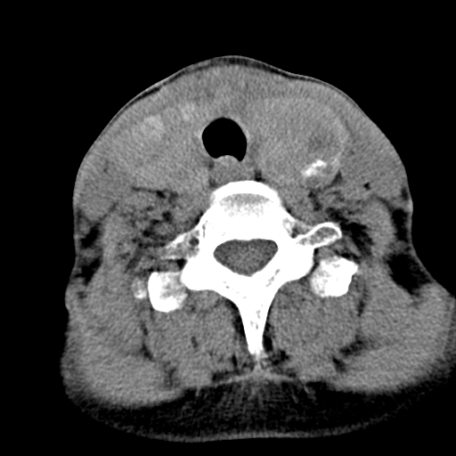

标题: CT24010:患者女56岁双侧甲状腺摘除术后一月复查,患者现感 [打印本页]

标题: CT24010:患者女56岁双侧甲状腺摘除术后一月复查,患者现感

甲状腺术后复发,现在甲状腺区域仍有密度不均匀之软组织密度影。

甲状腺区域密度不均匀密度影,应该是术后改变,要鉴别是否复发,建议增强检查。

“甲状腺摘除术后一月复查”,有病理吗?考虑术后复发,可能是恶性,颌下及左侧颈部淋巴结有肿大。

考虑术后复发,并颈部淋巴结肿大。请结合临床。

双侧甲状腺肿大,周围结构不清,术后复发时间有点短,考虑出血并感染。